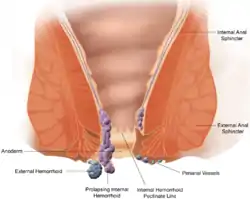

Pectinate line labeled at bottom center. | |

The pectinate line (dentate line) is a line which divides the upper two-thirds and lower third of the anal canal. Developmentally, this line represents the hindgut-proctodeum junction.

It is an important anatomical landmark in humans, and several distinctions can be made based upon the location of a structure relative to this line:

| Hemorrhoids classification | internal hemorrhoids (not painful) | external hemorrhoids (painful) |